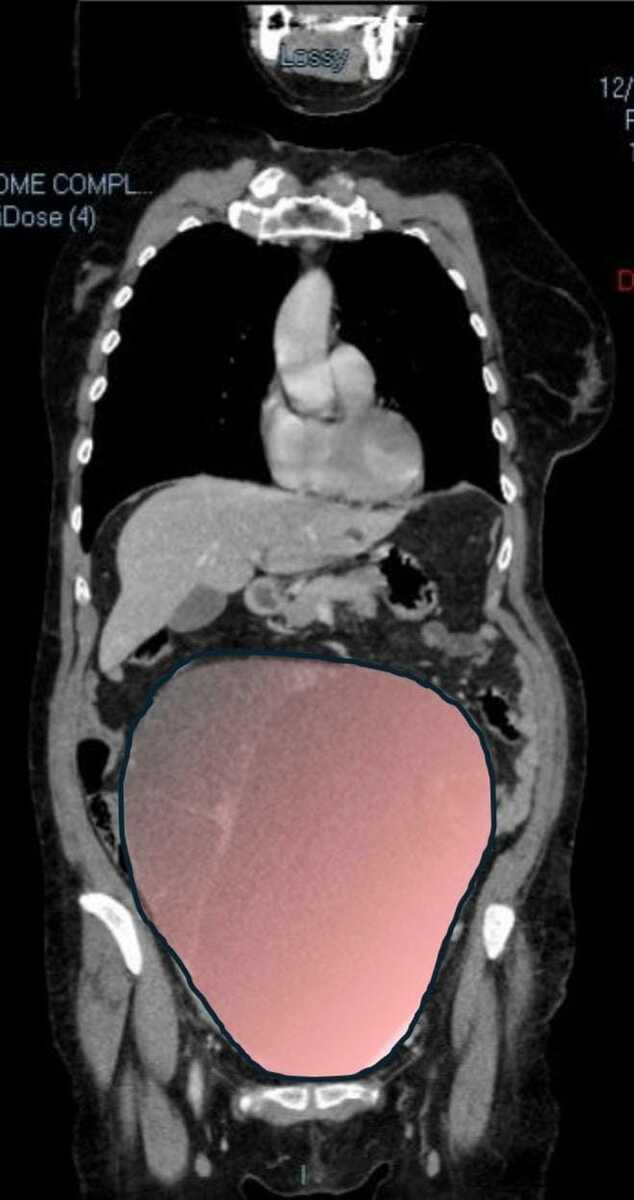

Per mesi la gigantesca cisti ovarica, con un diametro di circa 28 centimetri, è rimasta nascosta, senza dare segnali evidenti. La paziente non si era accorta di nulla. L’allarme è scattato quando la massa, associata alla presenza di una seconda neoplasia intestinale, ha iniziato a comprimere il colon, provocando sintomi acuti ed improvvisi fino a una grave difficoltà intestinale non più ignorabile.

Durante l’intervento emerge tutta la gravità della situazione. La gigantesca neoplasia ovarica viene asportata: pesa circa 6 chilogrammi, con un volume paragonabile a quello di una gravidanza gemellare a termine. Ma non è l’unica minaccia. I sintomi più pericolosi sono legati alla sofferenza intestinale, che richiede un intervento immediato e coordinato di più specialisti.